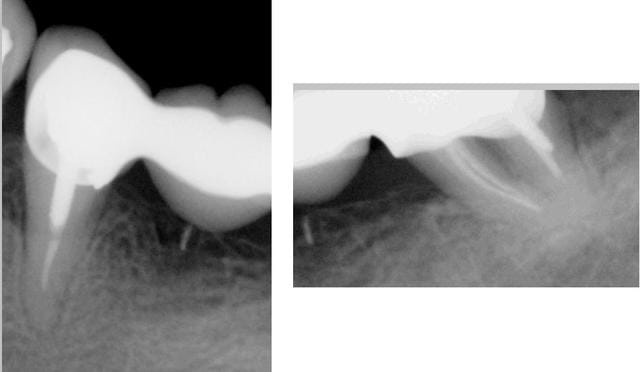

28/02/2016 à 00h36

celle là est pas mal mais en sens inverse.De la pate avant mais plus après pose de l'ic coiffe dans le palatin.

le patient s'en est aperçu 5 ans après suite à un signe d'appel.

Ce patient c'est moi. -)

Capteur VS plaque il n'y a pas photo. -)